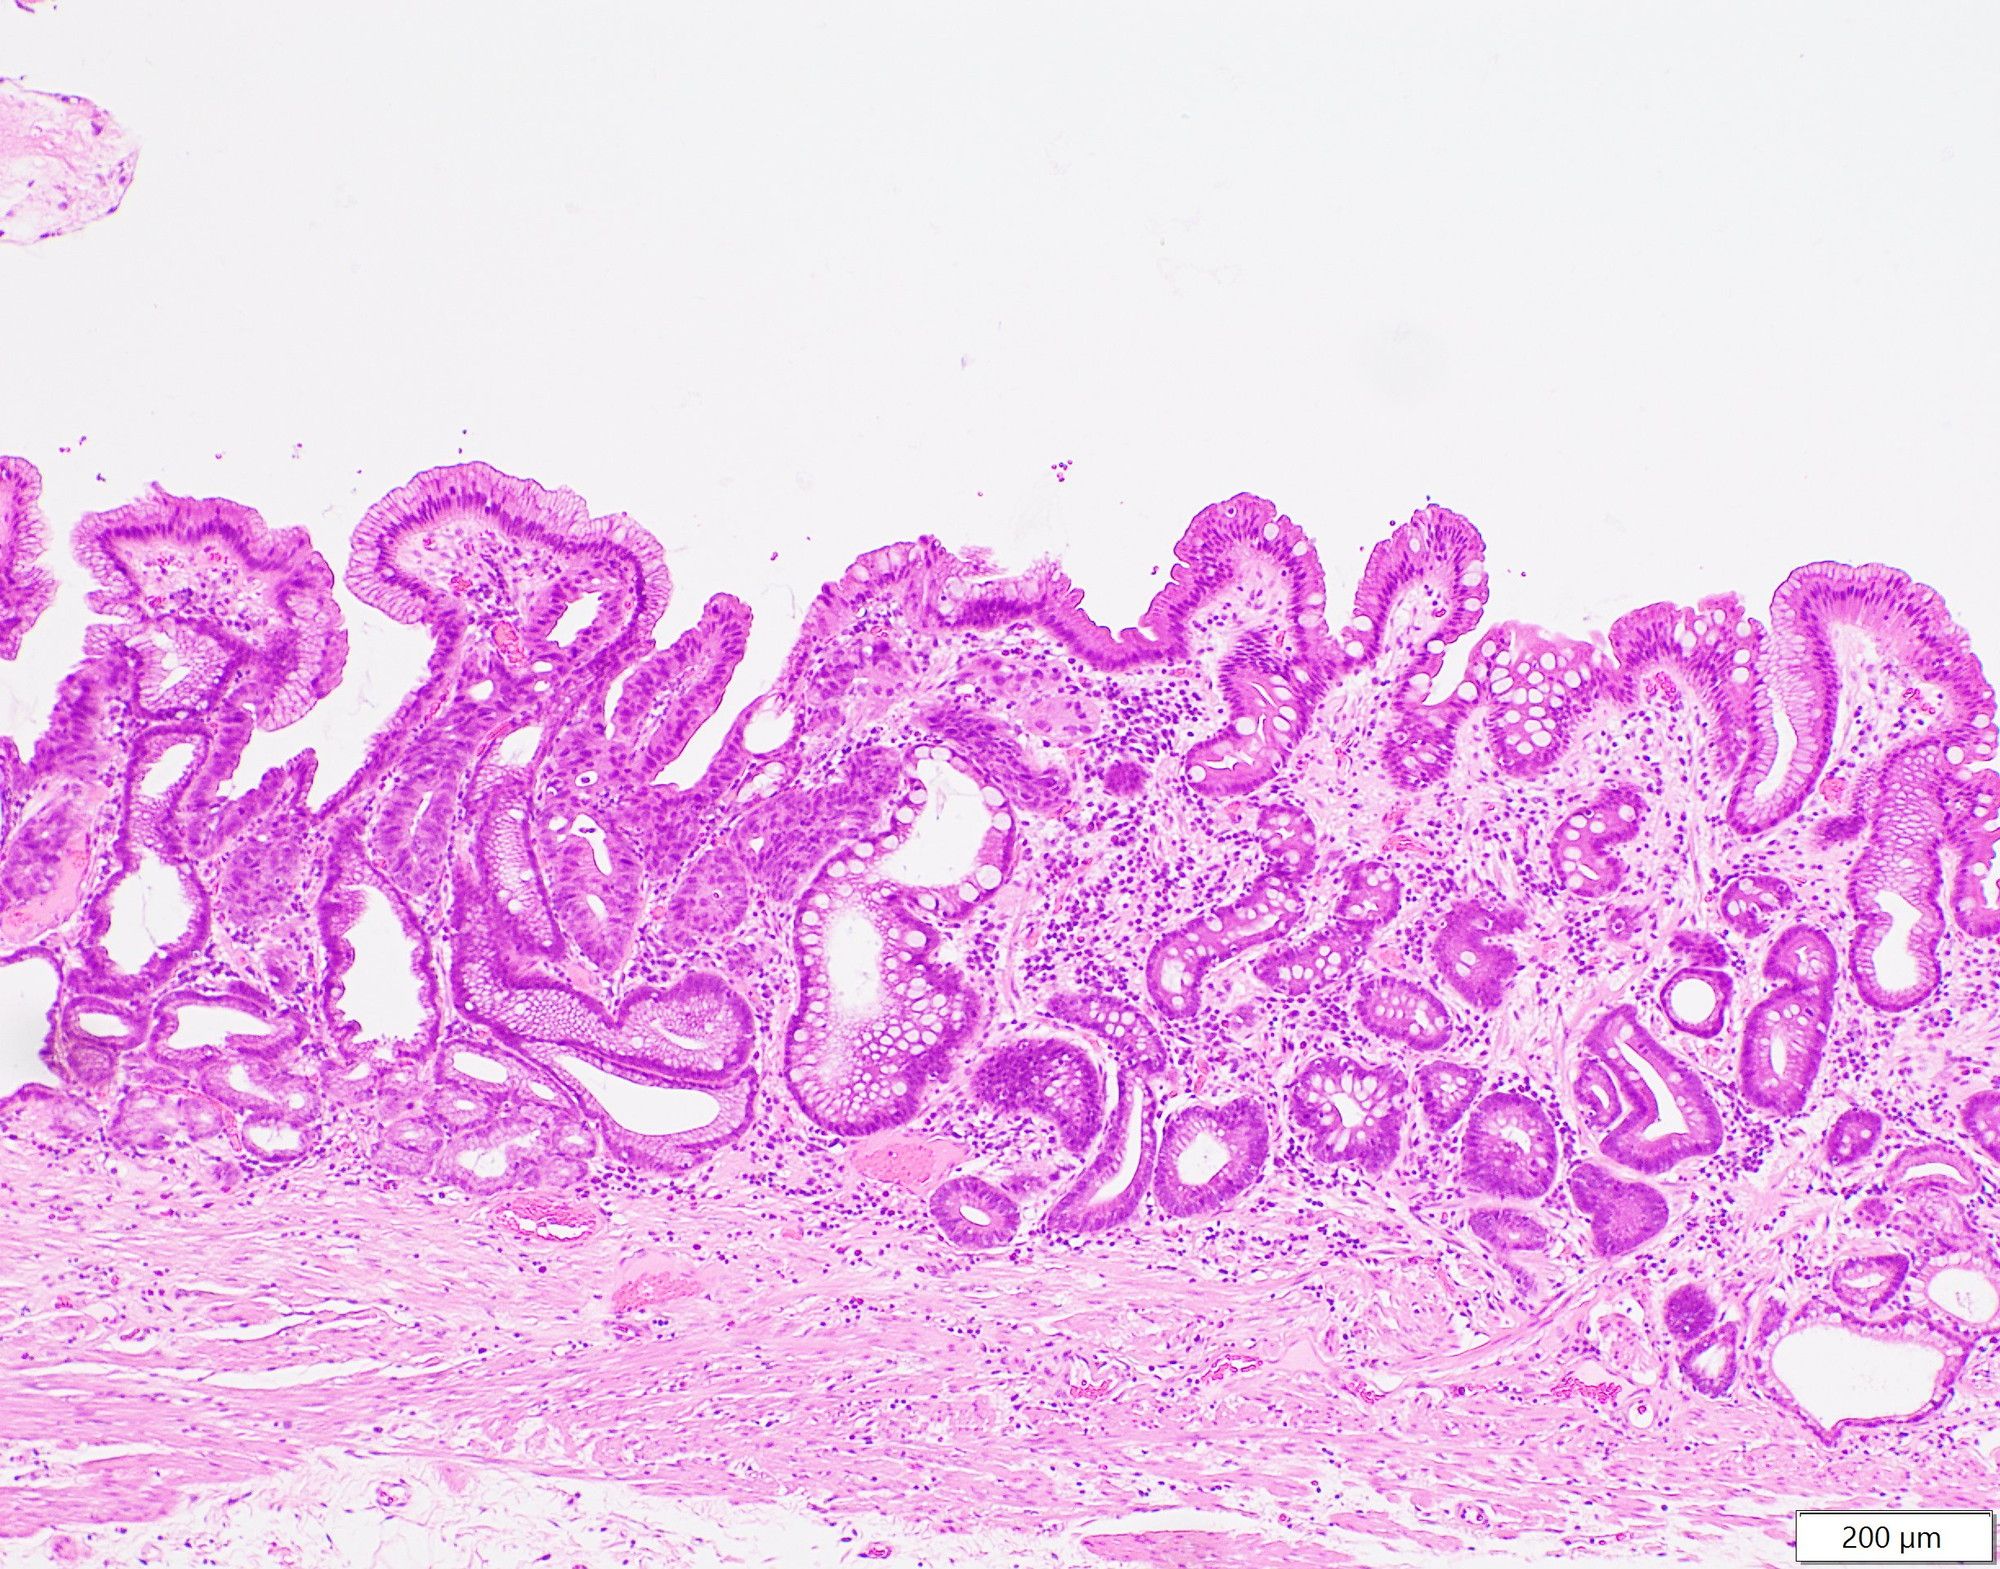

胃の粘膜内を広がるがんの写真